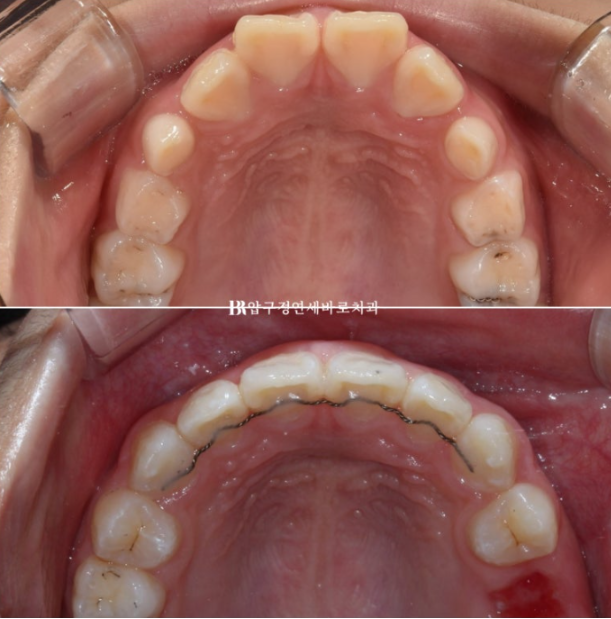

악궁확장을 통해 영구치 맹출공간 확보, 윗니 돌출 해소, 앞니 배열을 목표로 장치 제작에 들어갔습니다

한달 반을 기다려서 첫 장치를 낀 것은 22년 9월부터이고 23년 6월까지 9개월간 첫 세트 장치를 모두 낀 후 모습입니다.

배열은 상당히 가지런해졌고 그 사이 유치가 여러개 빠지며 영구치가 내려오는 중입니다.

악궁확장으로 넓어진 악궁, 그리고 가지런해진 앞니가 눈에 띕니다.

22.08~24.09

중심선도 정확히 맞고 과개교합도 해소가 되었습니다